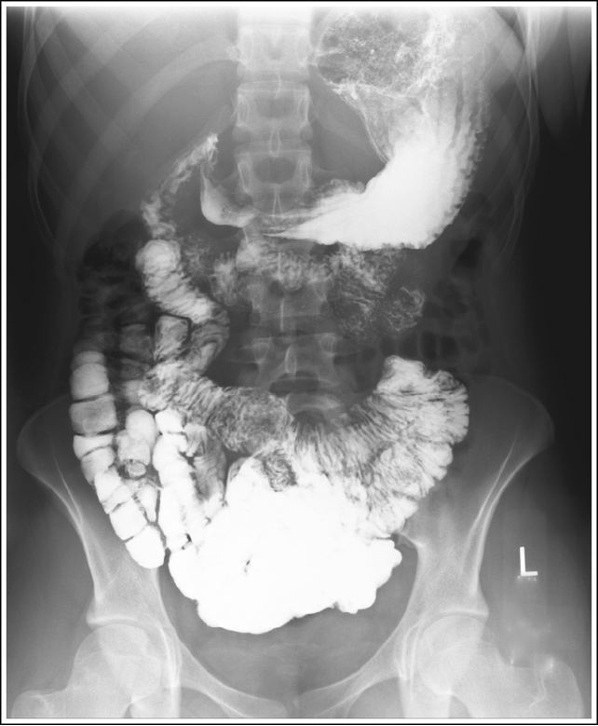

AP Stomach and Duodenum (CR and Positioning)

Supine or trendelenburg for hiatal hernia

14×17 IR

MSP at the level midway between the xiphoid process and the lower rib margin (1-2 inches above lower rib margin L1-L2)

If using 11×14 center between MSP and left lateral abdomen border at the level of L1-L2

Mark left side

Suspend respiration at the end of expiration

Shield gonads

PA Stomach and Duodenum (CR and Positioning)

Recumbent or erect

CR Recumbent - MSP at the level midway between the xiphoid process and the lower rib margin (1-2 inches above lower rib margin at L1-L2)

CR Erect - Center 3-6 inches lower than recumbent due to visceral movement

PA Stomach with proper positioning

PA Stomach with blotchy appearance within the barium. residual food particles

PA Stomach with fundus overexposed either due to mAs too high or AEC positioned beneath the barium filled body and pylorus

PA Stomach taken on inspiration, compressing and foreshortening the stomach

PA Stomach with proper expiration